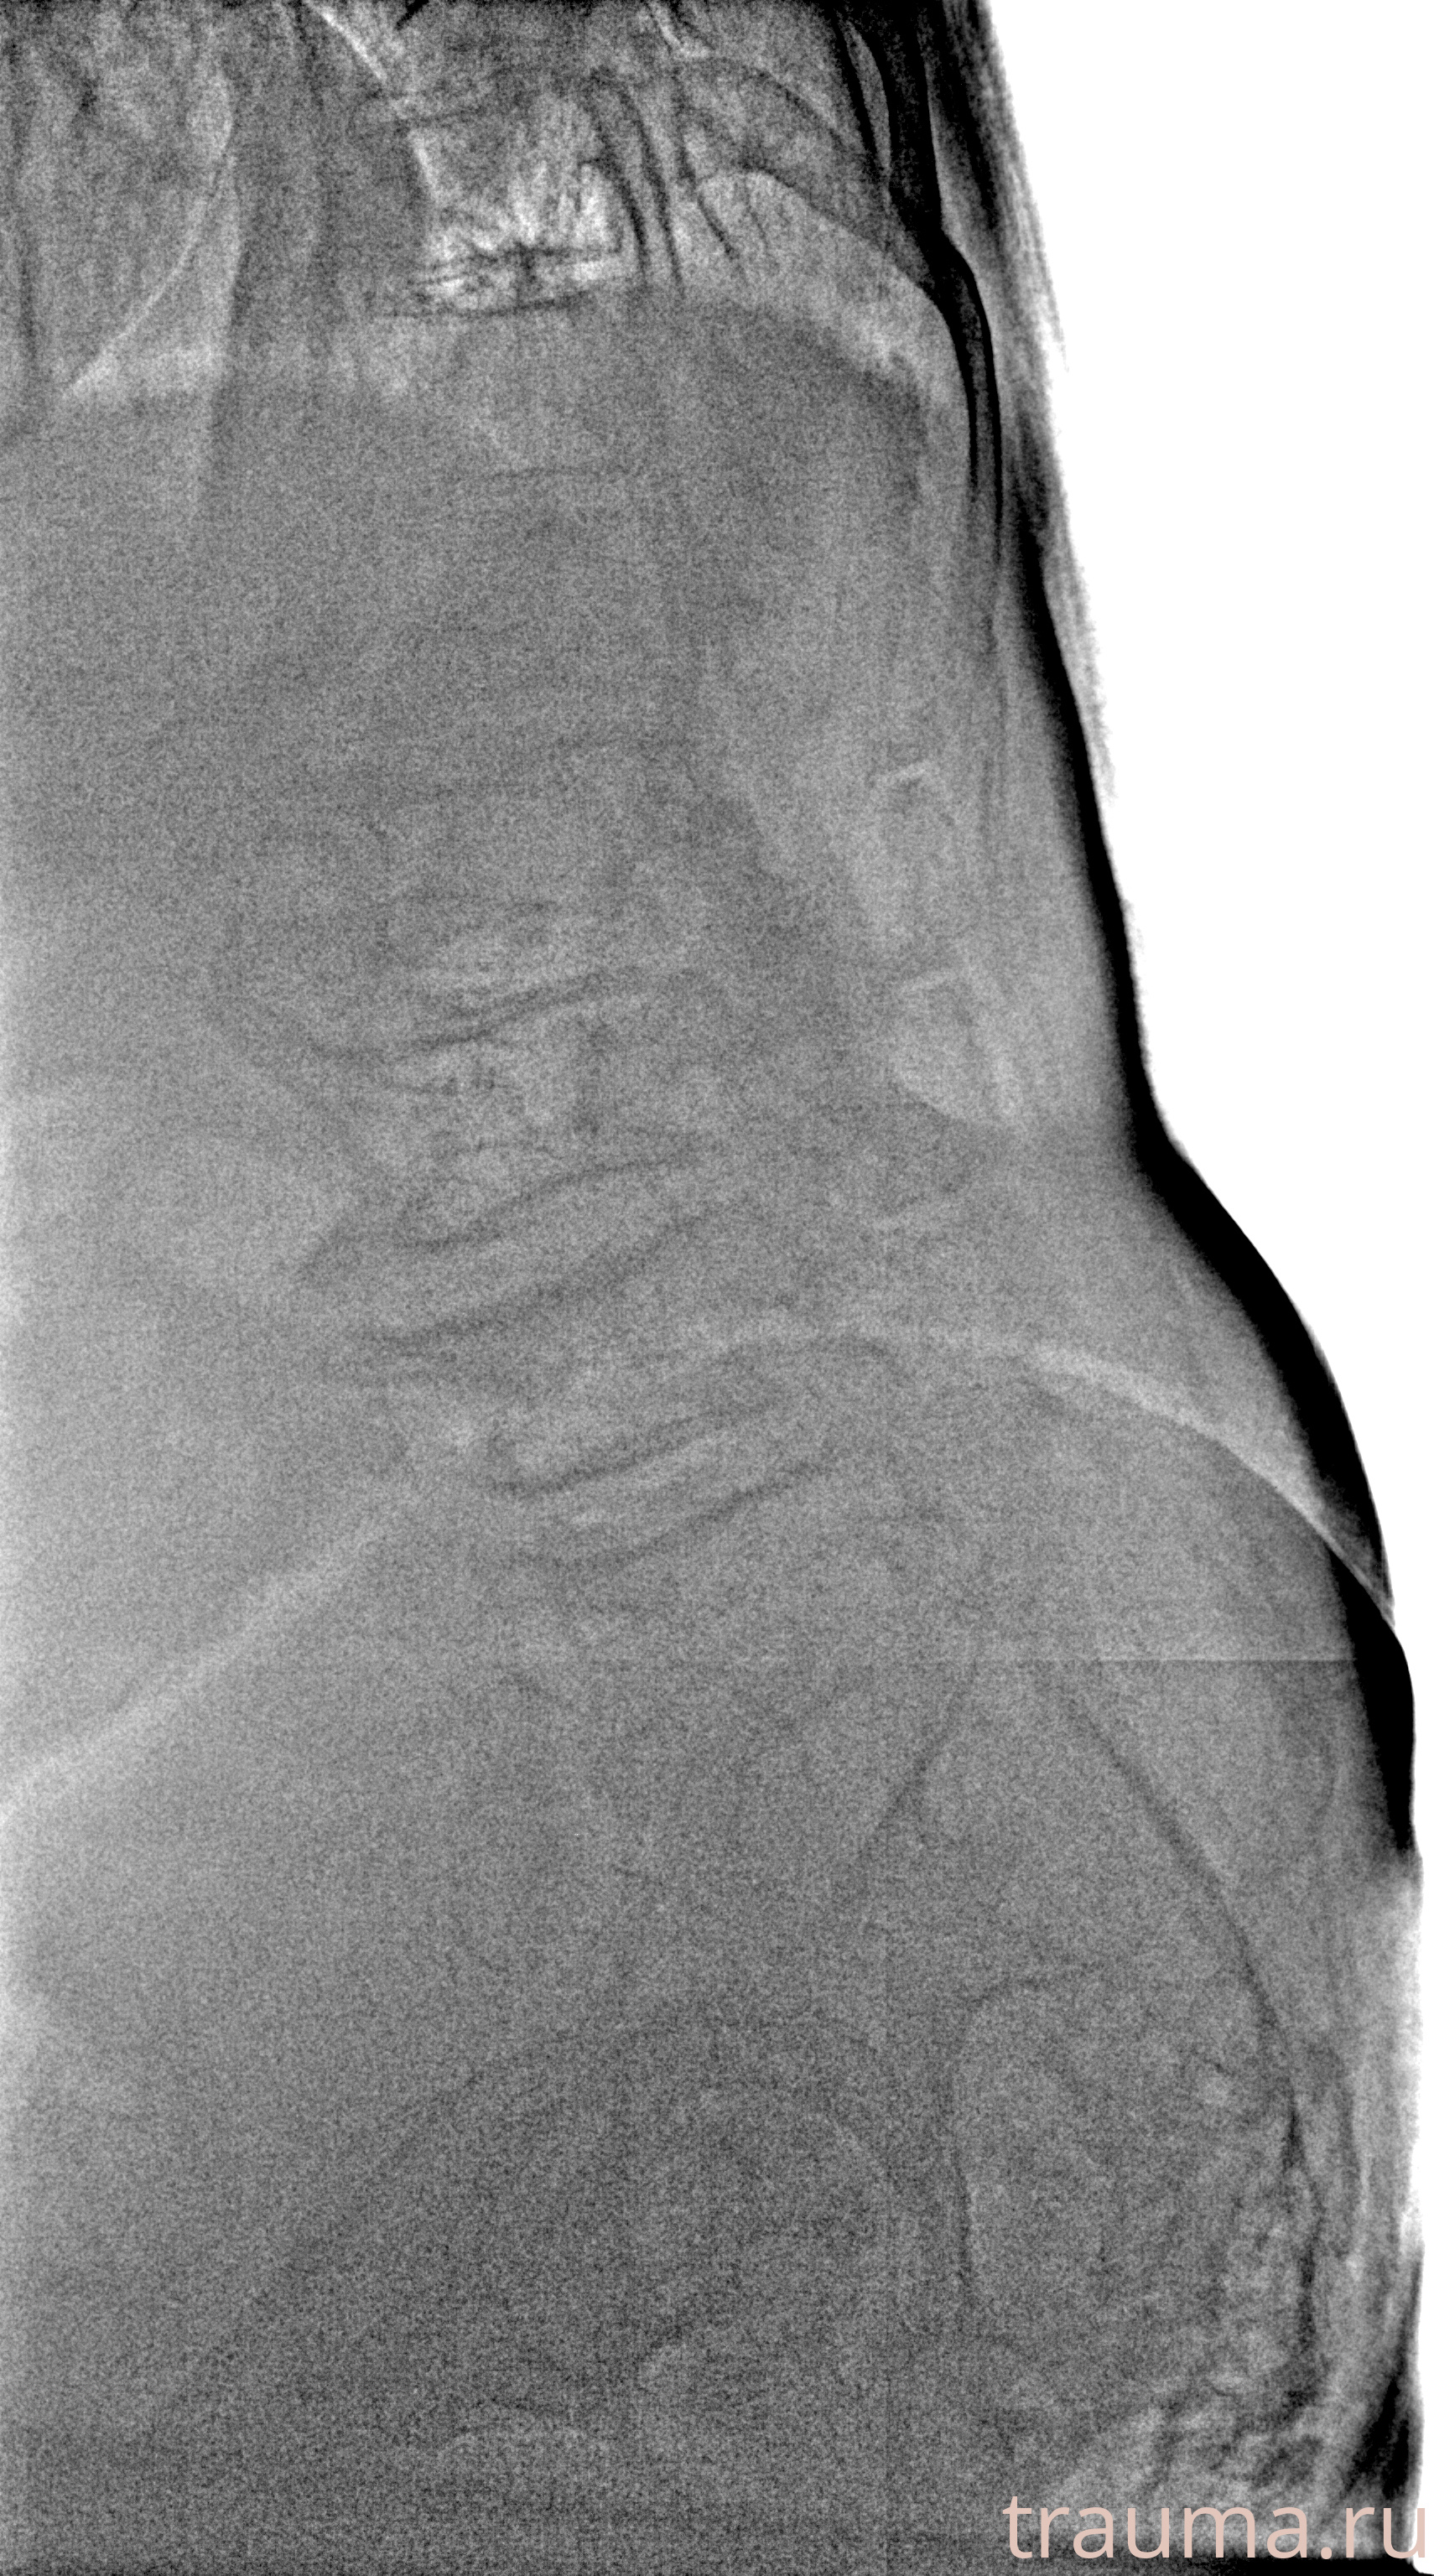

Рентген на дому: по вашему адресу приезжает врач-рентгенолог, травматолог-ортопед с мобильным рентгеновским аппаратом, проводит диагностику травмы или заболевания, делает необходимые рентгенограммы, дает рекомендации по дальнейшему лечению. Получить качественные снимки в домашних условиях возможно благодаря уникальной методике, разработанной МосРентген Центром для института  Склифосовского

при переломе шейки бедра и пневмонии от компании МосРентген Центр - партнера Института имени Склифосовского